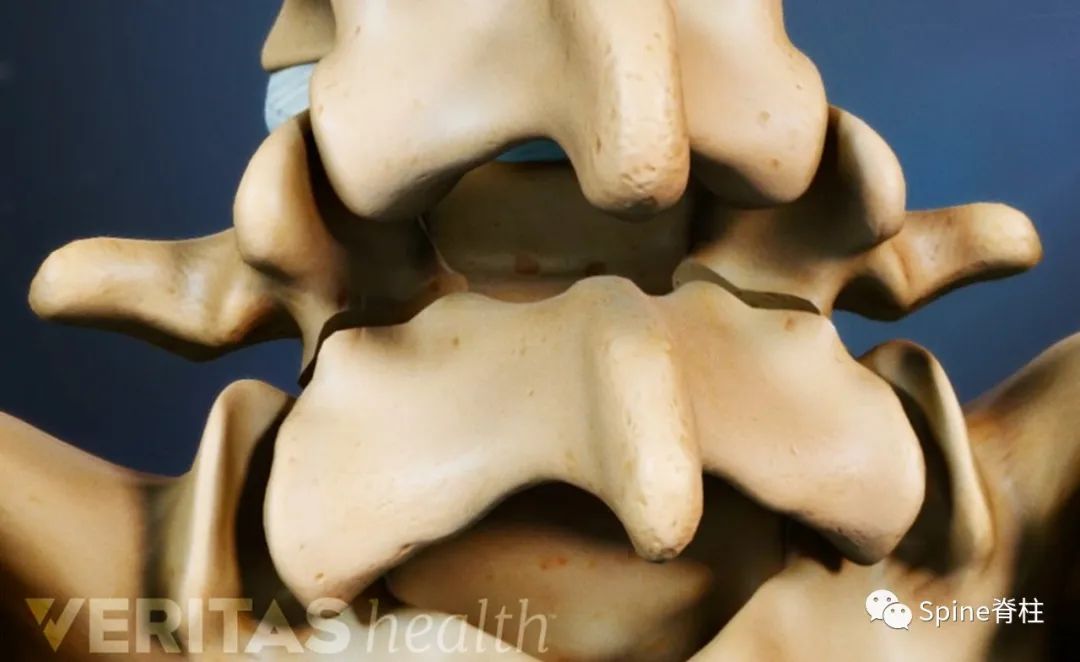

一、峡部的解剖

峡部 (pars interarticularis)是指上、下关节突之间椎弓的狭窄部分,又称为关节突间部 (人卫版八年制外科学)。因腰椎峡部裂相对比较常见,学者们的峡部研究常关注于腰椎。其实,从C2-L5各节段脊柱都是存在峡部。

峡部是在相邻节段平移运动中承受应力最大的部位, C2和L5的峡部最易发生创伤性或应力性骨折 (如C2的hangman骨折和L5峡部裂) 。峡部构成椎管侧隐窝的后部,并参与构成神经根管的后壁。

目前,学者们对腰椎峡部关注的较多,且研究的也比较深入。 McCulloch和Transfeldt提出了“侧方支撑” (lateral buttress) 的概念,认为腰椎峡部对介于其间的结构提供重要的结构性支撑,将腰椎峡部定义为连接下关节突的外上缘与横突/椎弓根的骨性桥梁。

在脊柱解剖和建筑结构上,侧方支撑用于在两个垂直结构之间分配荷载,降低其连接处的失效风险。PMID: 12221372